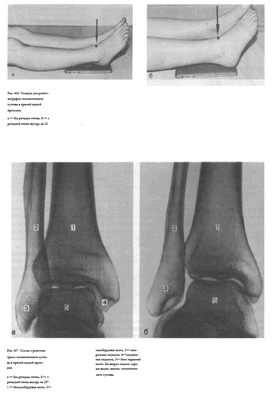

Укладка больного для выполнения снимка. Существуют два варианта укладки для выполнения снимка голеностопного сустава:

1. Снимок голеностопного сустава в прямой задней проекции без ротации стопы. Больной лежит на спине. Ноги вытянуты.

Сагиттальная плоскость стопы исследуемой конечности расположена перпендикулярно к плоскости стола, не отклонена ни кнутри, ни кнаружи. Кассету размером 18x24 см помещают под область голеностопного сустава с таким расчетом, чтобы проекция суставной щели, расположенной на 1 — 2 см выше нижнего полюса медиальной лодыжки, соответствовала бы средней линии кассеты. Пучок рентгеновского излучения направляют отвесно на центр проекции суставной щели голеностопного сустава (рис. 436, а).

2. Снимок голеностопного сустава в прямой задней проекции с ротацией стопы. Укладка отличается от предыдущей положением стопы, которую вместе с голенью ротируют на 15 — 20° кнутри. Положение больного, кассеты и центрация пучка рентгеновского излучения такие же, как и при укладке для снимка голеностопного сустава без ротации стопы

Информативность снимков. На снимках голеностопного сустава в прямой задней проекции выявляются дистальные отделы берцовых костей, медиальная и латеральная лодыжки, блок таранной кости и рентгеновская щель голеностопного сустава латерального отдела голеностопного сустава. Рентгеновская суставная щель на снимке голеностопного сустава с ротацией стопы выглядит в виде буквы «П», при этом ширина ее на всем протяжении одинаковая. Расширение латерального или медиального отдела суставной щели при наличии перелома лодыжек свидетельствует о подвывихе в суставе (рис. 438).

СНИМОК ГОЛЕНОСТОПНОГО СУСТАВА В БОКОВОЙ ПРОЕКЦИИ

Назначение снимка то же, что и снимка в прямой проекции.

Укладке больного для выполнения снимка. Больной лежит на боку.

Область голеностопного сустава латеральной поверхностью расположена на кассете. Стопу укладывают так, чтобы пятка плотно прилегала к кассете, что обеспечивает поворот стопы внутрь на 15 — 20°. Проекция суставной щели голеностопного сустава соответствует средней линии кассеты. Противоположная конечность согнута в коленном и тазобедренном суставах, перекинута вперед; бедро слегка приведено к животу. Пучок рентгеновского излучения направляют отвесно в центр кассеты через внутреннюю лодыжку (рис. 439).

Информативность снимка. На снимке выявляются дметальные отделы берцовых костей, проекционно накладывающиеся друг на друга, задний край суставной поверхности большеберцовой кости (так называемая «задняя лодыжка»; отрыв которой нередко имеет место при травмах), а также блок таранной кости, пяточная кость. При плотном прилегании наружной поверхности пятки к кассете сагиттальная плоскость стопы устанавливается под углом 15 — 20° к кассете, и на снимке достигается совпадение блоков таранной кости. В таких случаях рентгеновская суставная щель голеностопного сустава имеет форму правильной дуги равномерной ширины на всем протяжении (рис. 440).